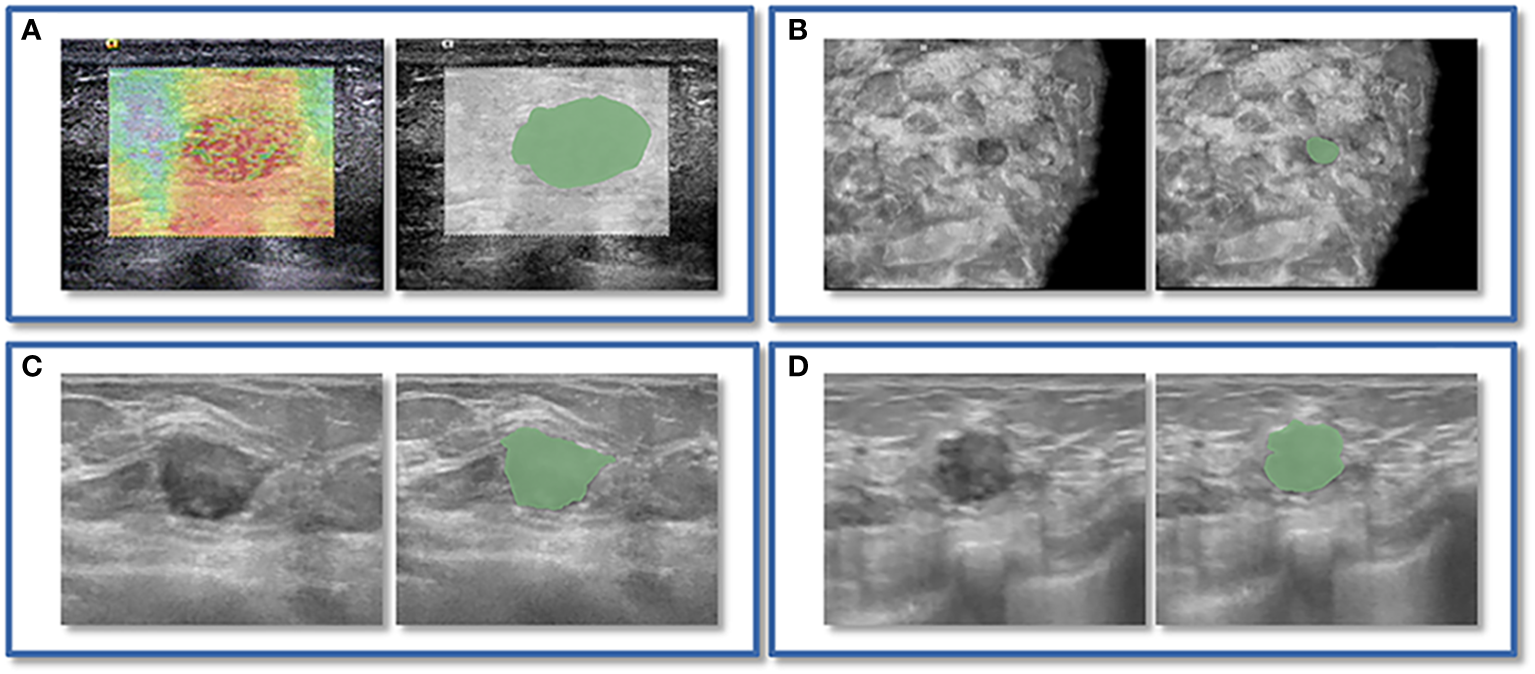

Figure 2

An instance of manually delineating a region of interest (ROI). The strain elastography (SE) and automated breast volume scanner (ABVS) images of a 41-year-old female with a solid hypoechoic lesion measuring approximately 16x11x12mm on her left breast. The lesion was irregular in shape, parallel in position, with still well-defined borders, sharp margins, and scattered microcalcifications visible internally, and exhibited no significant posterior echogenicity change or retraction in the coronal plane, and the ultrasound elasticity score was 4, finally, the lesion was classified as BI-RADS category 4a. Pathological examination confirmed it as invasive ductal carcinoma. ROI segmentation was performed on both the SE image (A) and ABVS coronal image (B), with delineation along the boundary of the lesion followed by uniform outward expansion of its edges by 3 mm to encompass some surrounding tissue.ROI segmentation was performed on ABVS transverse (C) and sagittal (D) images, respectively, and meticulous delineation was performed along the lesion’s contour and borders on these two views.